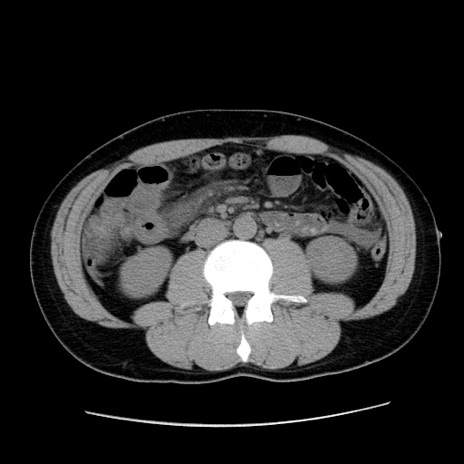

症例36(横断像)

【症例】20歳代 男性

【主訴】心窩部痛

【現病歴】今朝より上腹部痛あり。一旦軽快していたが再度出現したため救急要請。昨日夕に白身の魚を含む刺身を食べた。

【身体所見】BP 136/89mmHg、HR 74/min、BT 37.0℃、腹部:膨満、軟、心窩部に圧痛あり。反跳痛なし、筋性防御なし、腸雑音やや亢進あり。

【データ】WBC 17700、CRP 0.48